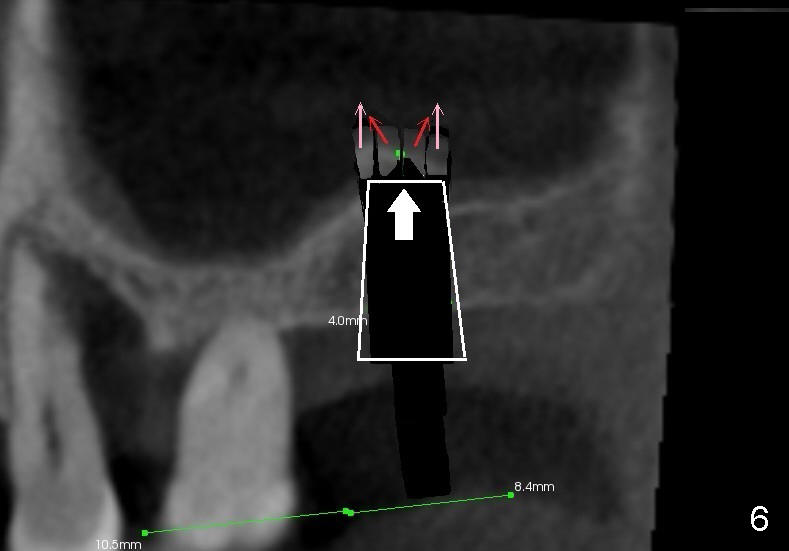

Fig.1 is a sagittal section of the posterior maxilla. A 2 mm (in diameter) round straight osteotome (white box) is going to initiate osteotomy and sinus lift. When the osteotome penetrates the bone initially, the latter is going to be condensed and pushed laterally (mesiodistally) and apically (Fig.2,3 arrows).

As the osteotome advances, some of the bone is brought apically (Fig.3 insert). The tapping with the thin osteotome should be stopped when penetration of the sinus floor is felt. The latter undergoes green stick fracture in a small area (Fig.4 arrows).